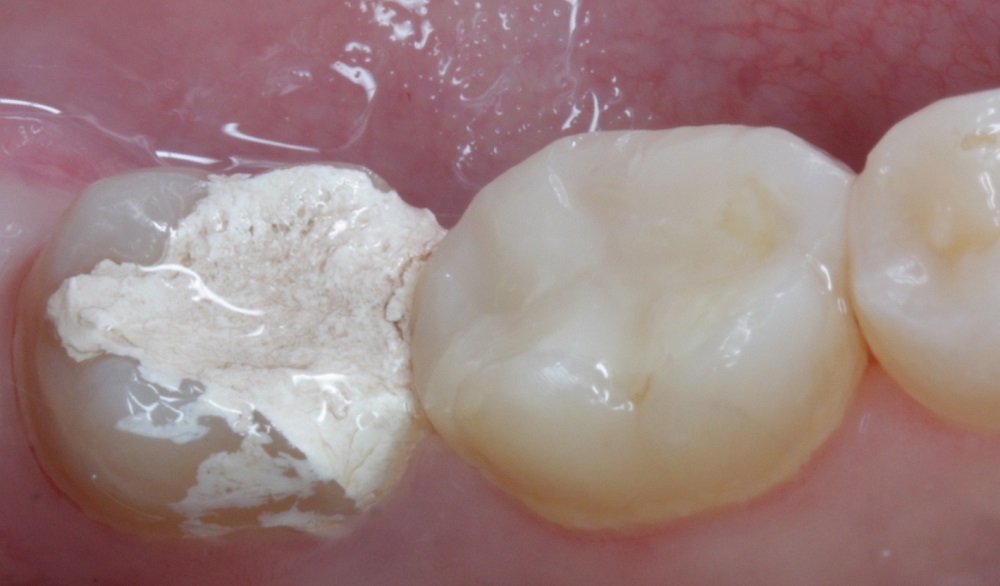

♦️ Воспаление корня зуба